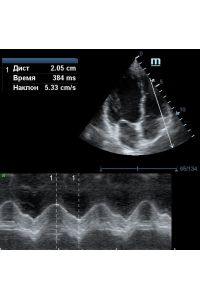

MAPSE - амплитуда движения латерального кольца митрального клапана, позволяет рассчитать фракцию выброса по формуле EF = 4.8 × MAPSE (mm) + 5.8, очень быстрый и гораздо более точный («прародитель Strain») метод чем широко распространенный метод Teicholtz. В современных приборах можно легко добавить свою формулу при отсутствии ее в стандартном калькуляторе. Главным условием является проведение линии М-режима параллельно стенке левого желудочка в апикальном четырехкамерном сечении, что легко достигается при использовании функции Free Xros.